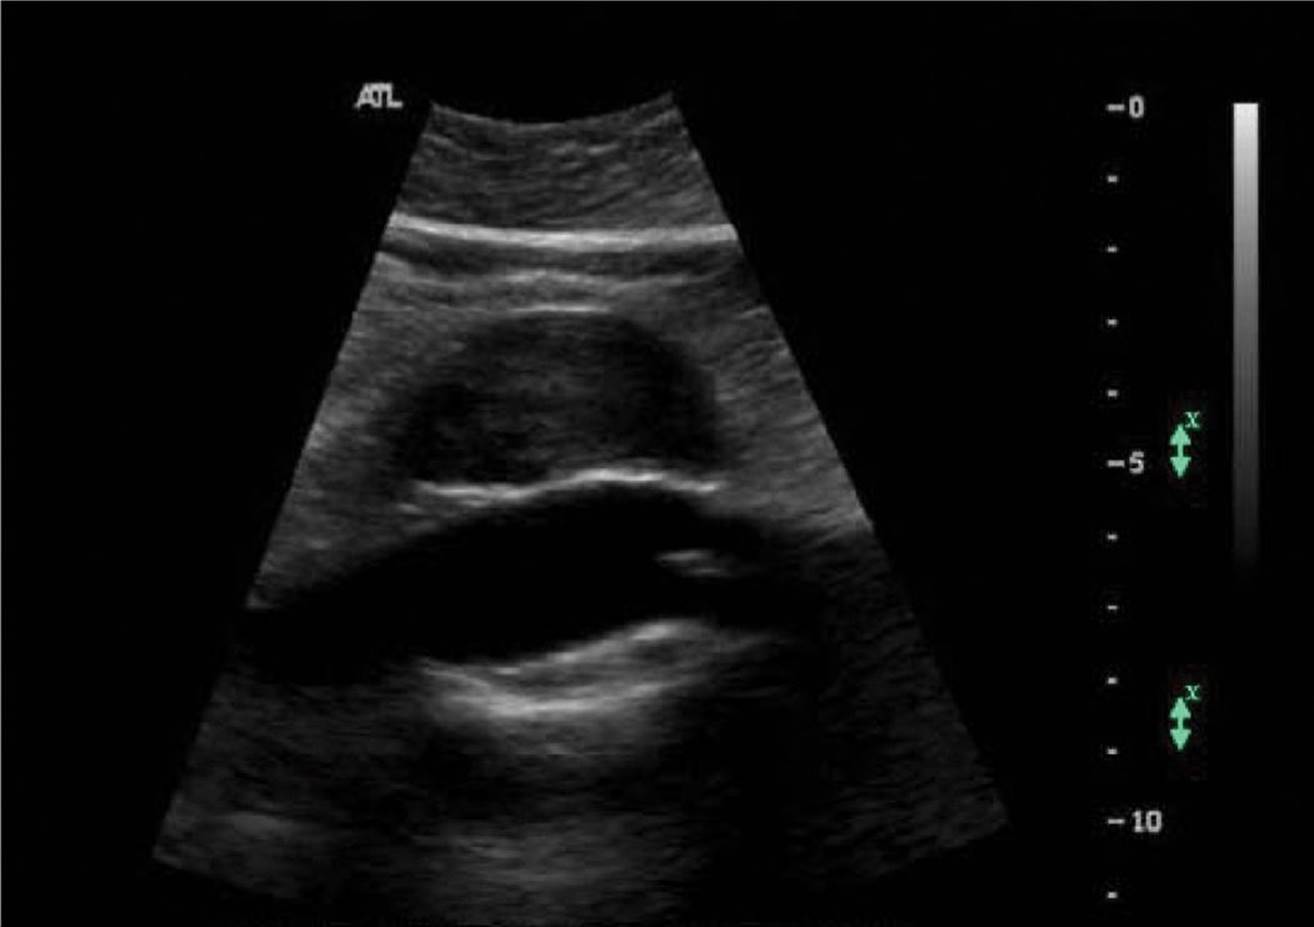

Sonographic and Doppler Characteristics. Thrombosis of the IVC causes dilation at the site of outflow obstruction. Acute thrombus will appear hypoechoic and a free-floating thrombus tail may be seen in the very acute phase (Fig. 11–28). The IVC will be noncompressible or partially compressible with transducer pressure applied directly over the vein in the transverse imaging plane. As the thrombus ages, it will initially increase in echogenicity but then progresses through a variety of characteristics ranging from acoustic heterogeneity with anechoic regions to homogeneity. The acoustic features return to heterogeneity and the vein walls contract as the thrombus becomes chronic.

FIGURE 11–28. Real-time longitudinal image of the inferior vena cava demonstrating acute, free-floating thrombus.